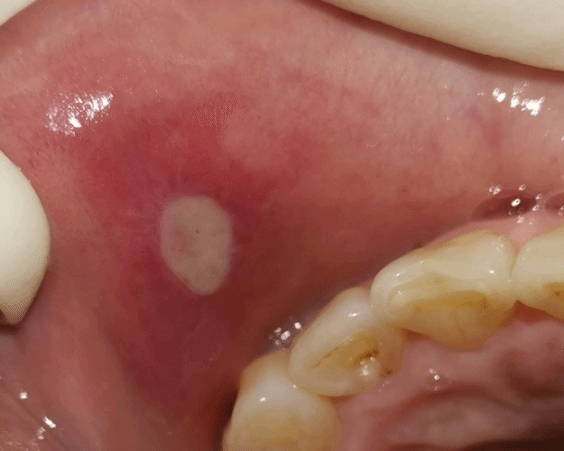

口腔黏膜专业号主要诊治范围包括单独发生在口腔黏膜上的原发的疾病,也可包括全身性疾病的口腔表现,以及同时发生于皮肤和口腔黏膜上的疾病。比较常见的口腔黏膜病,如复发性口腔溃疡、扁平苔藓、口腔念珠菌病、慢性唇炎、口腔白斑、慢性盘状红斑狼疮等。口腔黏膜病的治疗方法主要包括局部治疗、全身药物治疗、中西医结合疗法、以及手术切除等。

复发性口腔溃疡                                                     口腔扁平苔藓